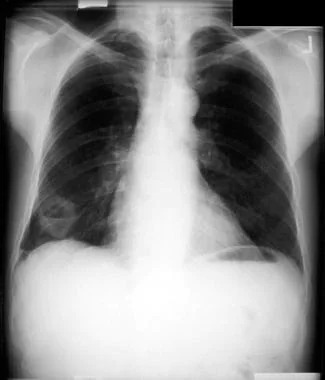

Does a chest X-ray show lung cancer?

X-rays aren’t as good as CT scans for showing a tumor in your lungs, especially at earlier stages. Tumors might be too small to see on an X-ray or can be blocked from view by other structures in your body (like your ribs). X-rays can’t diagnose lung cancer — they can only show your provider if there’s something suspicious that they should look into further.

Imaging

Chest X-rays and CT scans give your provider images that can show changes in your lungs. PET/CT scans are usually done to evaluate a concerning finding on a CT scan or after a cancer diagnosis to determine whether cancer has spread.